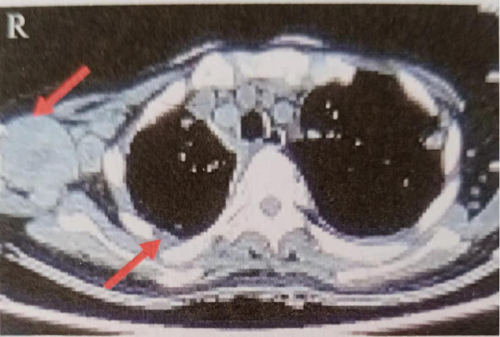

2018年7月10日行胸部CT示双侧胸廓对称,纵隔居中。右肺体积缩小,右侧胸腔可见大量胸腔积液,双侧肺野可见多发大小不一结节状高密度影,肺门及纵隔可见多发肿大淋巴结影,部分可见融合,肺动脉包绕受压,右侧胸膜可见不均匀结节样增厚,左侧胸腔可见液体密度影,右侧腋窝可见多发团块状、结节状软组织密度影,最大的约7.8cmx5.4cm,可见分叶,部分可见融合并可见液化坏死,增强扫描实性部分平均CT值约54HU(图1)。

图1胸部CT示右侧大量胸腔积液,右侧腋窝软组织密度影7.8cmx5.4cm